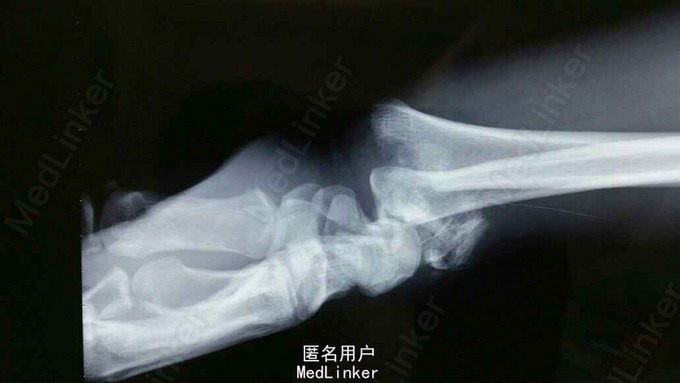

诊断:双尺桡骨远端粉碎性骨折 治疗:入院后,给予手法复位夹板固定,左手神经症状明显缓解,给予对症治疗,消肿后,于2015年8月27日行手术治疗。

请问大家,对于这种骨折是行外架+克氏针固定好,还是钢板固定好?